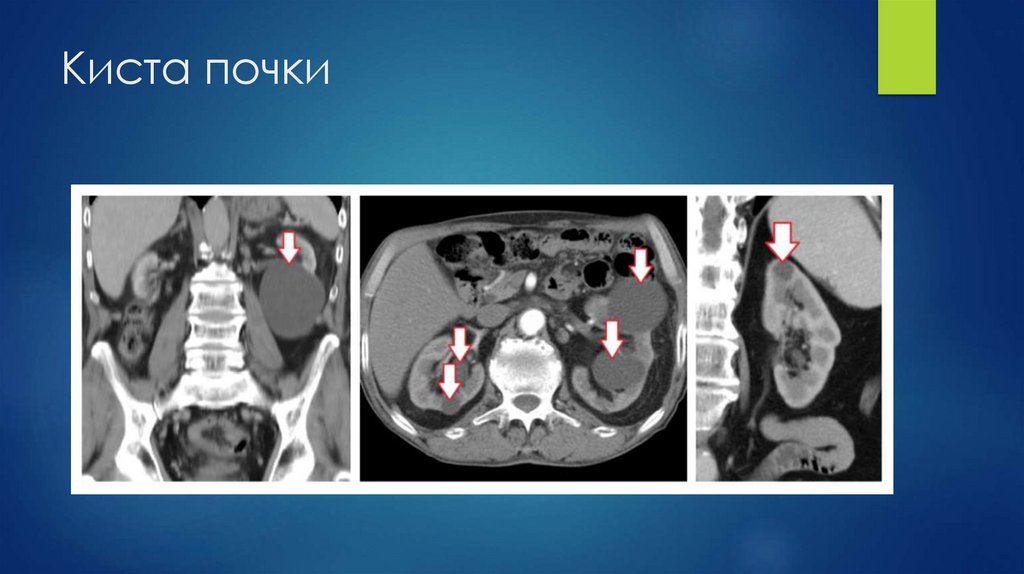

Киста почки

70. Киста почки